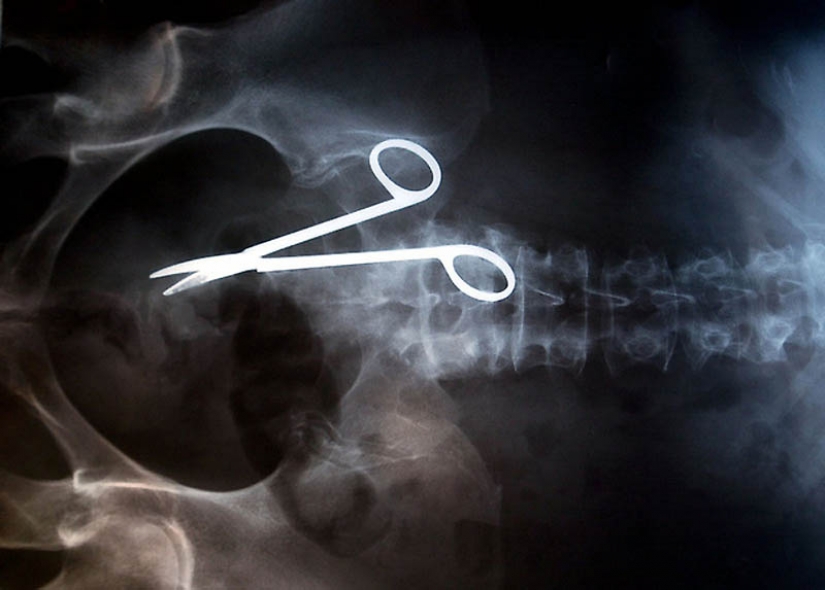

12. Tijeras quirúrgicas, accidentalmente olvidado en el cuerpo del paciente después de la cirugía. Las tijeras fueron descubiertos sólo 18 meses después de la operación, porque la mujer se quejó de un dolor constante en el intestino.